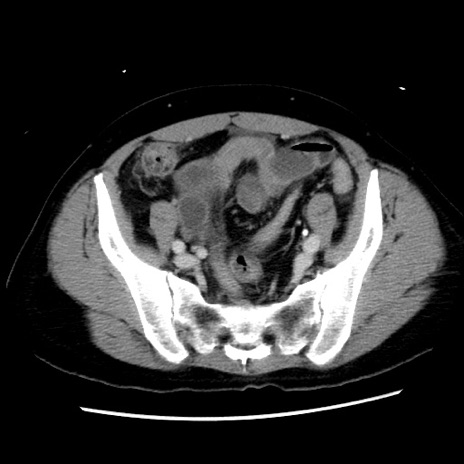

症例10(横断像)

【症例】 50歳代女性

【主訴】 腹痛

【現病歴】前日生レバーを食べた。今朝に排便あり。 昼前に突然発症の腹痛を生じ、当院救急外来を受診した。

【既往歴】 子宮筋腫にてで子宮全摘後

【身体所見】 意識清明、腹部:平坦、軟、下腹部やや左を中心に圧痛・反跳痛あり、筋性防御あり

【データ】WBC 7800、CRP 0.07